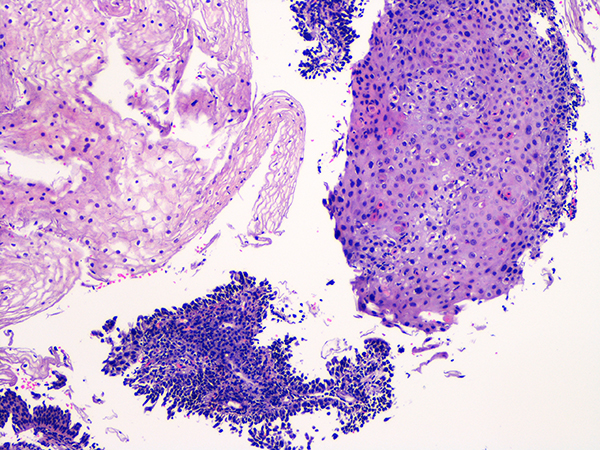

![]() Case 2

Soft Bx CIN 2 10x - Low Power |

Soft Bx CIN 2

40x - High Power